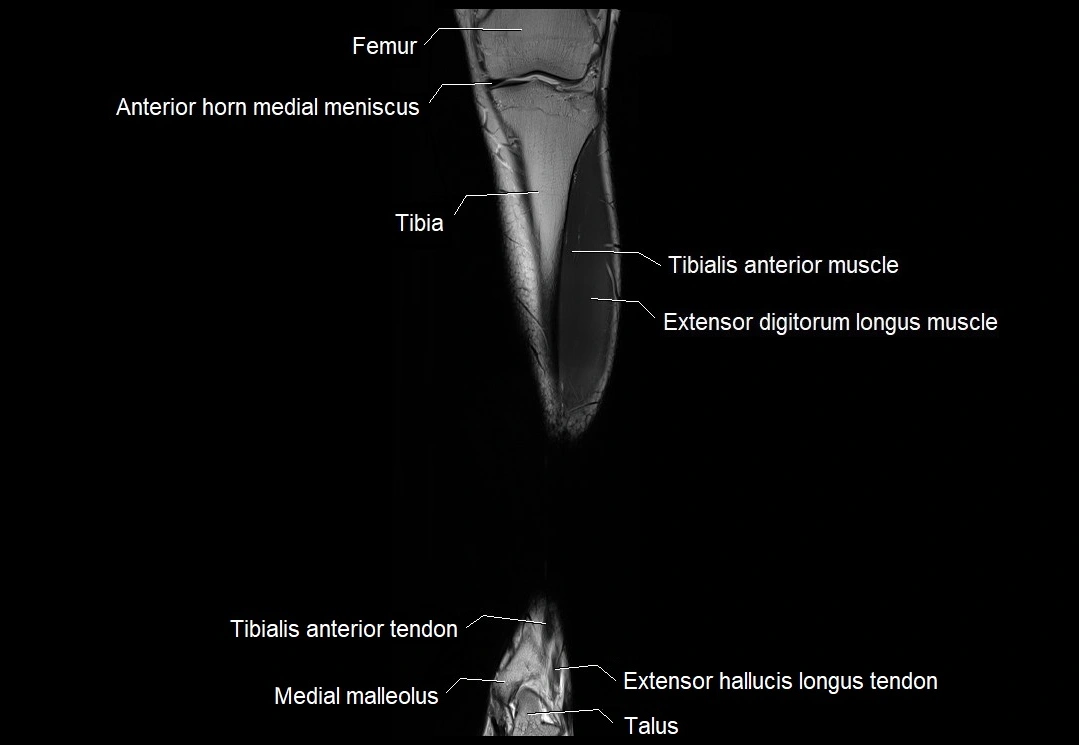

MRI image